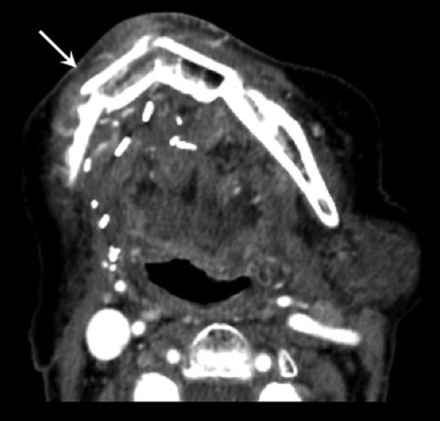

NI-RADS primary site category 2b: ill-defined asymmetric soft tissue. T4N0 oral cavity squamous cell carcinoma. CECT shows asymmetric full soft tissue around fibular reconstruction of the mandible (arrow). The linked management recommendation is shorter interval surveillance. Repeat CECT at 3 months showed no interval change (not shown). Subsequent clinical follow-up also demonstrated improvement and no disease recurrence.